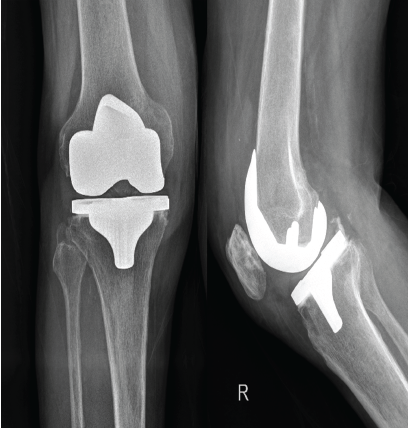

A Novel Seven-Day Abbreviated Two-Stage Exchange Arthroplasty with Intra-Articular Antibiotic Irrigation for Chronic Periprosthetic Joint Infection of the Knee: A Case Report

Nicolas S Piuzzi , Ignacio Pasqualini , Shujaa T Khan , Bryan D Springer , Brian C De Beaubien

………………………………p.119-125

Total Knee Arthroplasty following Genicular Artery Embolization: A Case Report

G Varun Prasad , Mohammad Salil , Jai Thilak

………………………………p.126-130